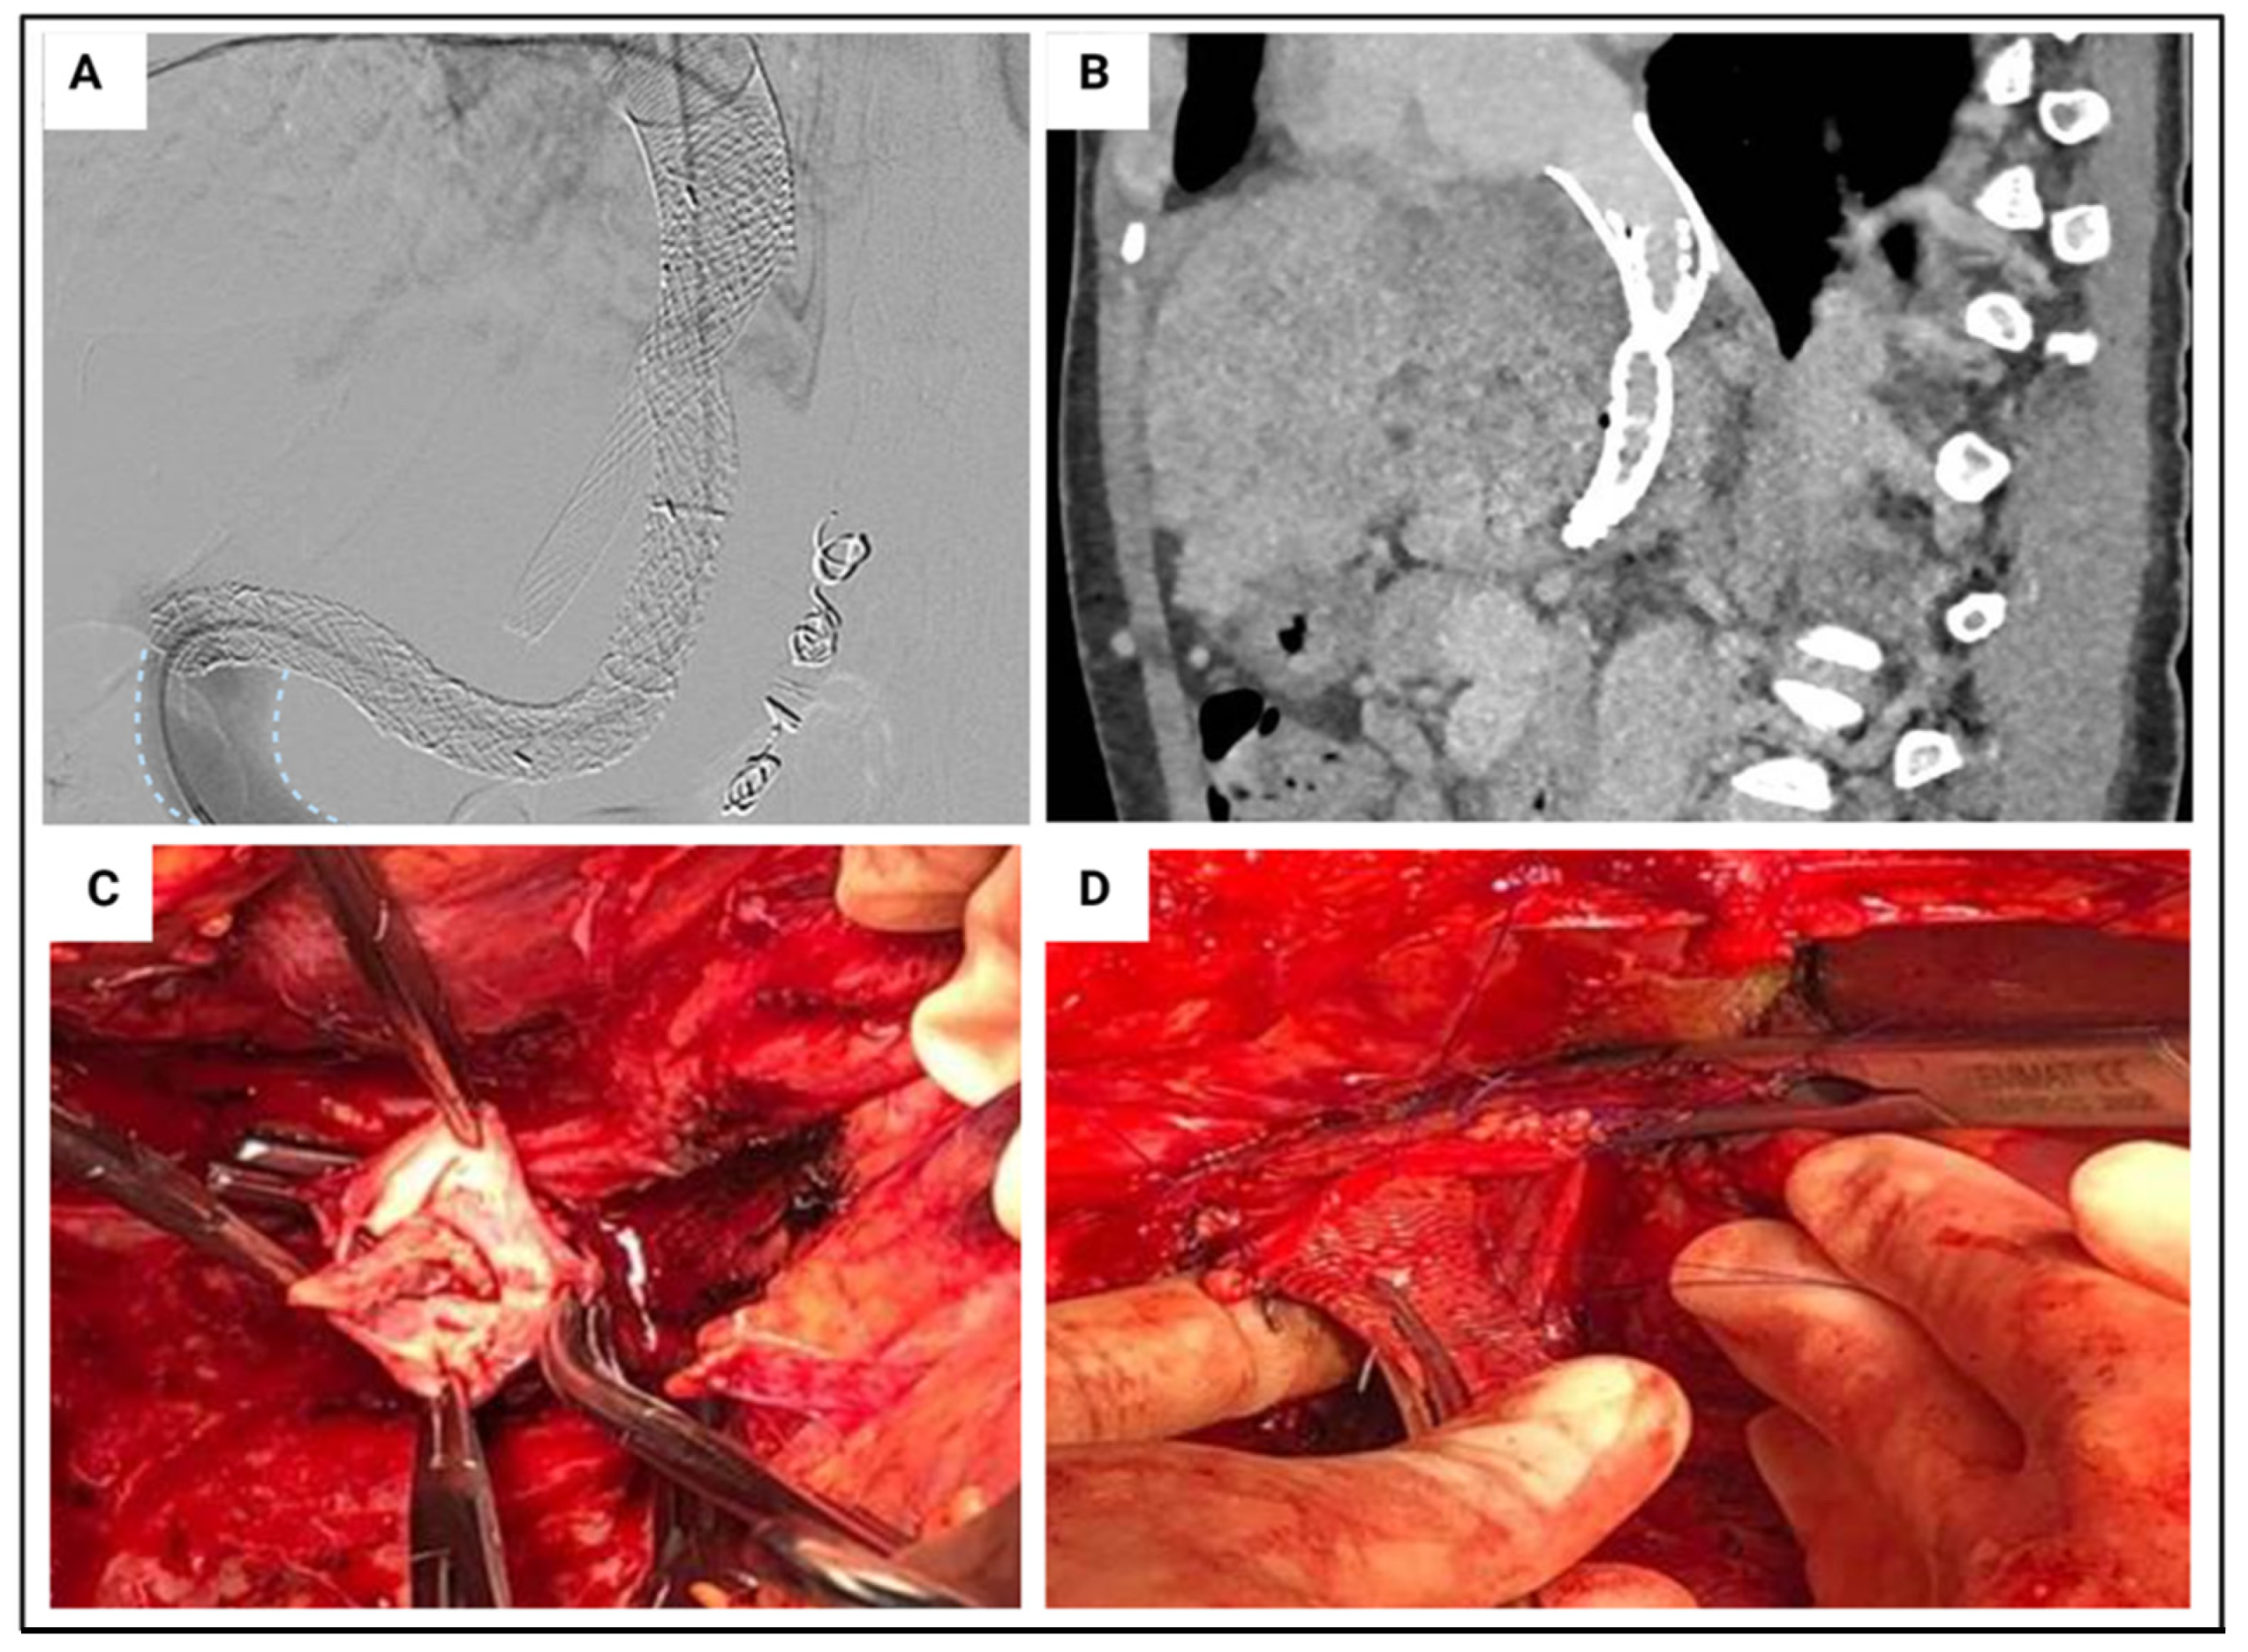

5.3. Portal Vein Thrombosis

| Grade | Extension |

|---|---|

| Grade I | <50% of the vessel lumen with or without minimal extension into the superior mesenteric vein (SMV). |

| Grade II | >50% occlusion of the PV, including total occlusions, with or without minimal extension into the SMV. |

| Grade III | Complete thrombosis of both PV and proximal SMV. Distal SMV is open. |

| Grade IV | Complete thrombosis of the PV and proximal, as well as distal, SMV. |